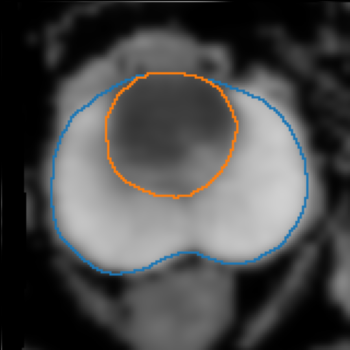

The emergence of multi-parametric magnetic resonance imaging (mpMRI) has had a profound impact on the diagnosis of prostate cancers (PCa), which is the most prevalent malignancy in males in the western world, enabling a better selection of patients for confirmation biopsy. However, analyzing these images is complex even for experts, hence opening an opportunity for computer-aided diagnosis systems to seize. This paper proposes a fully automatic system based on Deep Learning that takes a prostate mpMRI from a PCa-suspect patient and, by leveraging the Retina U-Net detection framework, locates PCa lesions, segments them, and predicts their most likely Gleason grade group (GGG). It uses 490 mpMRIs for training/validation, and 75 patients for testing from two different datasets: ProstateX and IVO (Valencia Oncology Institute Foundation). In the test set, it achieves an excellent lesion-level AUC/sensitivity/specificity for the GGG$\geq$2 significance criterion of 0.96/1.00/0.79 for the ProstateX dataset, and 0.95/1.00/0.80 for the IVO dataset. Evaluated at a patient level, the results are 0.87/1.00/0.375 in ProstateX, and 0.91/1.00/0.762 in IVO. Furthermore, on the online ProstateX grand challenge, the model obtained an AUC of 0.85 (0.87 when trained only on the ProstateX data, tying up with the original winner of the challenge). For expert comparison, IVO radiologist's PI-RADS 4 sensitivity/specificity were 0.88/0.56 at a lesion level, and 0.85/0.58 at a patient level. Additional subsystems for automatic prostate zonal segmentation and mpMRI non-rigid sequence registration were also employed to produce the final fully automated system. The code for the ProstateX-trained system has been made openly available at https://github.com/OscarPellicer/prostate_lesion_detection. We hope that this will represent a landmark for future research to use, compare and improve upon.